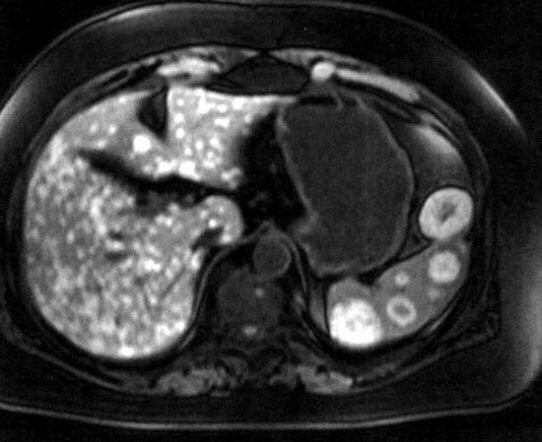

Методы динамического контрастирования печени на МРТ

Раздел: Снимки-подсказки